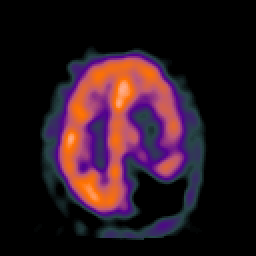

SPECT TC Study #2 -- Slice #37

[Home][Help][Clinical][Tour 1][Tour 2][Tour 3] Slice 37